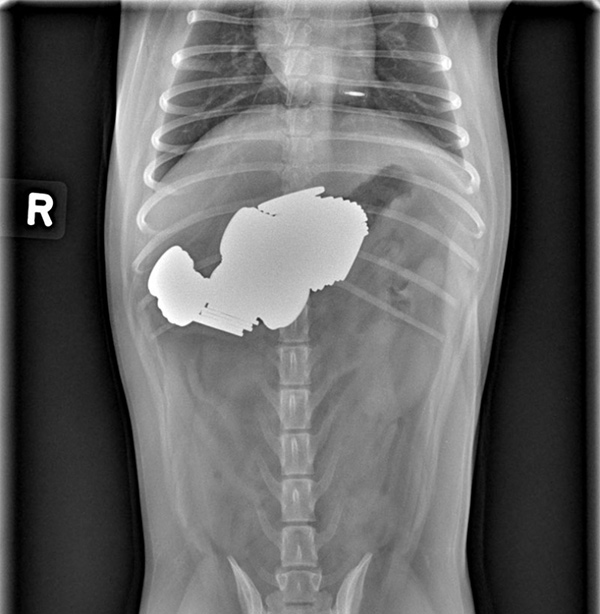

Best French Bulldog X Ray in the world Don t miss out bulldogs